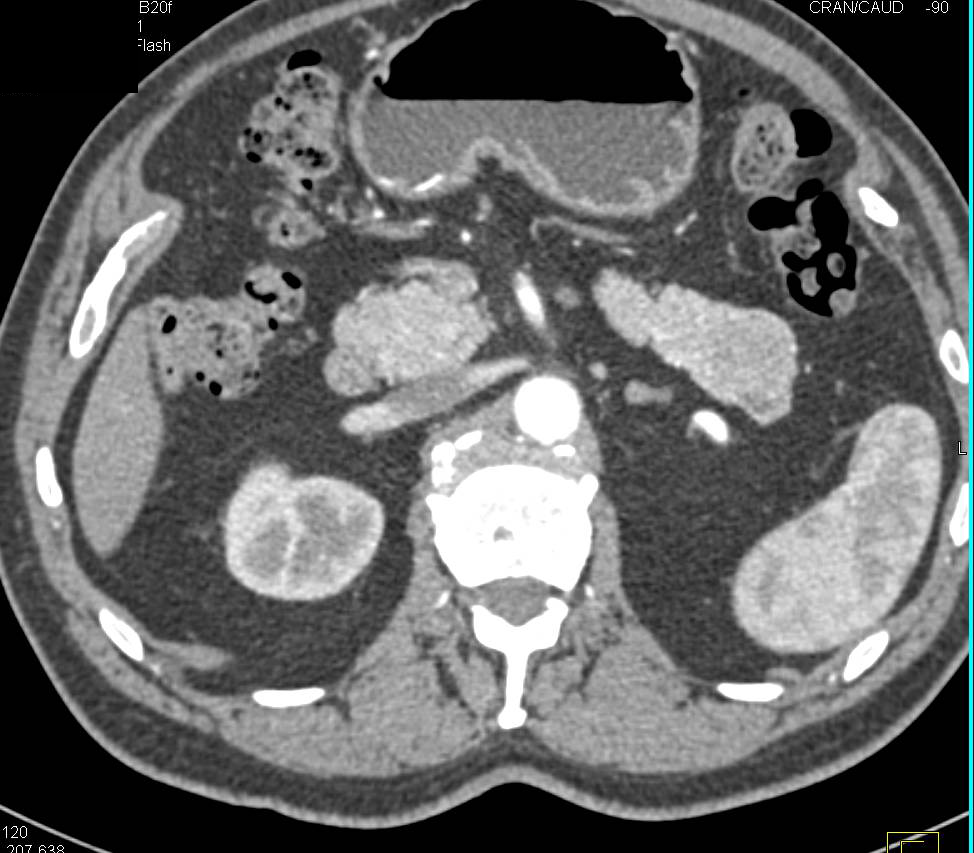

Pancreatic Cancer with Superior Mesenteric Vein (SMV) Thrombus